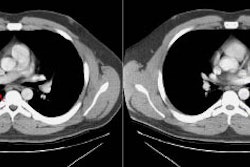

obstructive pneumonia. Bronchial carcinoids radiologically manifest as hilar or

perihilar masses, with or without associated atelectasis, pneumonia,

bronchiectasis, or mucoid impaction. At computed tomography, an anatomic

relationship of these tumors to a bronchus is usually seen, and they may show

contrast material enhancement or calcification. In rare cases, carcinoids occur